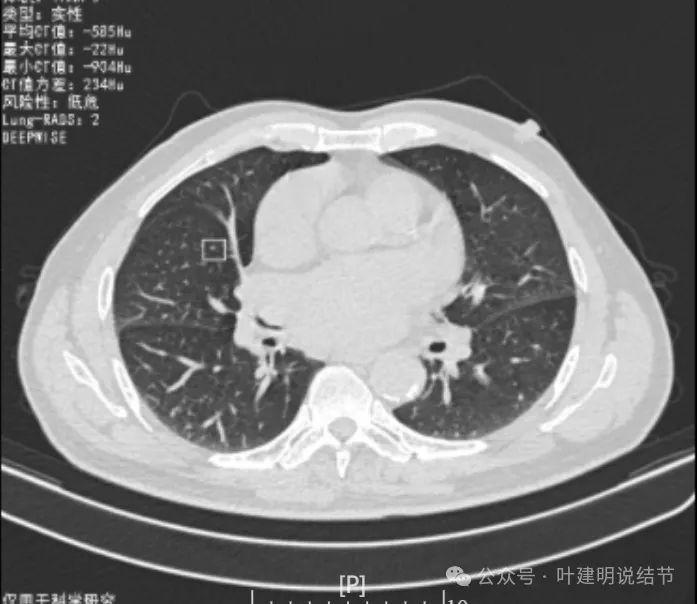

我们先来看2022年3月主要病灶的影像:

右上叶结节实性,密度高,边缘平整,轮廓清楚,像良性些。

右下似见微小结节,实性,与边上小血管截面不太好区分,过小没什么临床意义,能随访。

左下胸膜下实性结节,轮廓稍模糊,密度较高,边缘较光,像淋巴结些,能随访。

再看2022年8月复查时AI报告找出来的影像:

多是微小实性结节,主要的仍是右上与左下的这两处,较3月时无明显变化。而右下原来似有微小结节处这次并不明显。